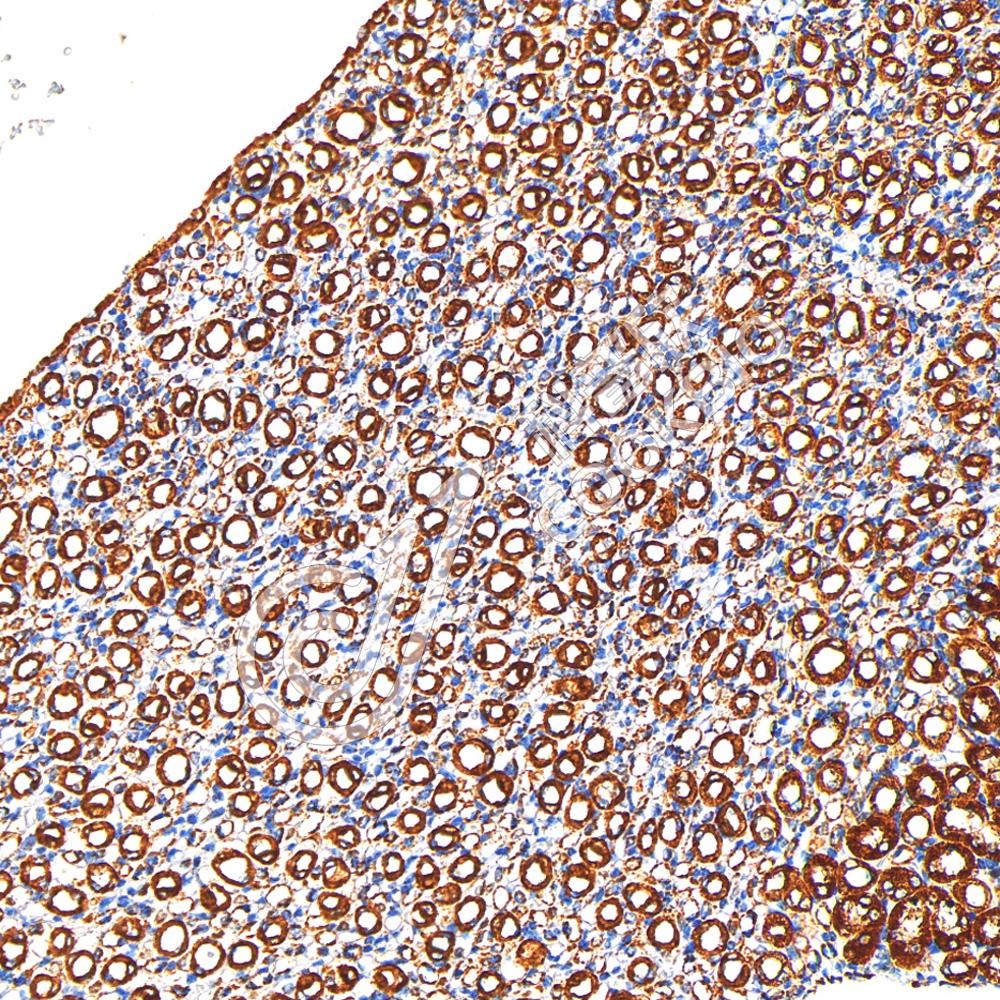

IHC检测COX IV蛋白(货号 K5450039).

样品: 小鼠肾, 4%多聚甲醛 (货号KSG1101) 固定12-24小时.

抗原修复: 柠檬酸抗原修复液(干粉, pH 6.0) (KSG1201), 高压锅均匀喷气计时2分钟.

—抗: 1: 600稀释, 4℃ 孵育过夜.

二抗: S-vision免疫组化多聚二抗(山羊抗兔),即用型 (货号KB3906), 室温孵育20分钟.